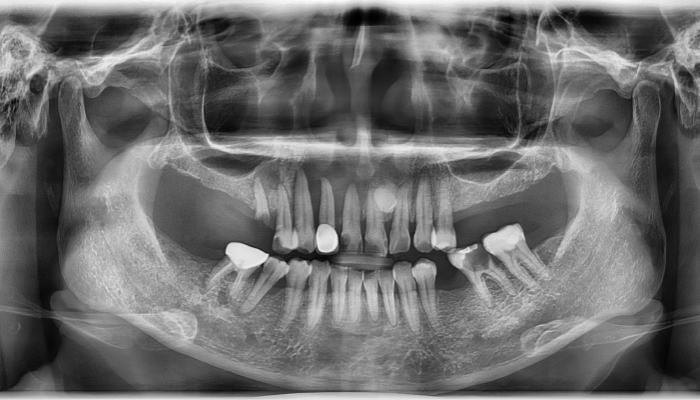

상악동거상술 수술사진

상악동거상술 전후 사례

• 식립 전

식립 후

• 식립전

식립후